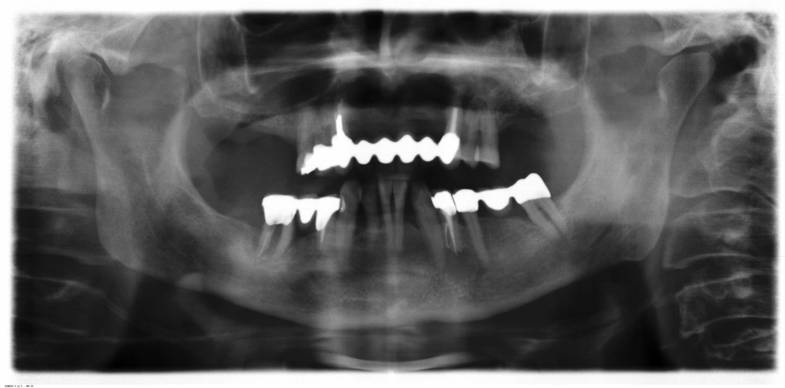

Dabei ist zu beachten, dass aufgrund der langen Liegezeit von Zahnamalgam (10 Jahre oder länger) bereits eine einzige Füllung eine Vielzahl von Beschwerden auslösen kann. Selbst wenn Amalgamfüllungen nach Jahren herausgebohrt werden (Vorsichtsmaßnahmen beachten!) und ungiftige Ersatzstoffe benutzt werden, so ist doch bereits viel Quecksilber (Hg) in den Körper gelangt. Es speichert sich im Fettgewebe, Knochen oder Gehirn ab und hat laut Aussagen von Dr. Daunderer oder Dr. Klinghardt eine biologische Halbwertzeit von 30 Jahren und länger. Eine fachgerechte Entgiftung ist daher unbedingt erforderlich. Das Gleiche gilt für wurzelbehandelte Zähne, die häufig Eiterherde bilden (oft unerkannt oder unbemerkt) und durch ihren jeweiligen Organbezug für schwere gesundheitliche Störungen verantwortlich sein können. Eine Röntgen-Panorama-Aufnahme (OPG) kann das Ausmaß der Belastung zumindest im Zahn-Kiefer-Bereich sichtbar machen. Für den homöopathischen Praktiker bedeutet dies, dass eine genaue Repertorisation bzw. Differenzialdiagnose in manchen Fällen kaum oder unmöglich realisiert werden kann, solange im Körper des Betroffenen die Auswirkungen schädigender Umwelteinflüsse ihr Unwesen treiben. Diese „unterhaltenden Ursachen“, wie Hahnemann sie nannte, erzeugen ihre eigenen, umweltbedingten Symptome, die einen Homöopathen bei der Mittelbestimmung in die Irre führen können. Werden sie abgestellt, verändert sich das Symptomenbild meist drastisch und eine homöopathische Behandlung ist u.U. kaum noch nötig oder es tritt jetzt die von Fremdsymptomen befreite chronische Krankheit zutage, die nun in gewohnter Weise repertorisiert werden kann und zu einer verläßlicheren und nachhaltigeren Mittelverschreibung führt. Natürlich gelingen viele homöopathische Heilungen auch ohne Berücksichtigung von schädlichen Umwelteinflüssen. Dafür kann es verschiedene Gründe geben. Eine individuell unterschiedlich stark ausgeprägte Kompensationsleistung (Lebenskraft) des Körpers kann beispielsweise umweltbedingte manifeste Symptome zeitweilig verhindern und somit den Homöopathen in die Lage versetzen, die relevanten Zeichen einer Erkrankung klar zu erkennen und eine dementsprechende Mittelverschreibung vorzunehmen. Die durch ein gefundenes Simile einsetzenden Heilreaktionen dürfen jedoch nicht darüber hinwegtäuschen, dass es höchst ungewiß bleibt, wie lange dieser fragile Gesundheitszustand aufrecht erhalten werden kann, wenn Störquellen und Gifte ungehindert weiter auf den Körper einwirken. Buch- und Videoempfehlungen: